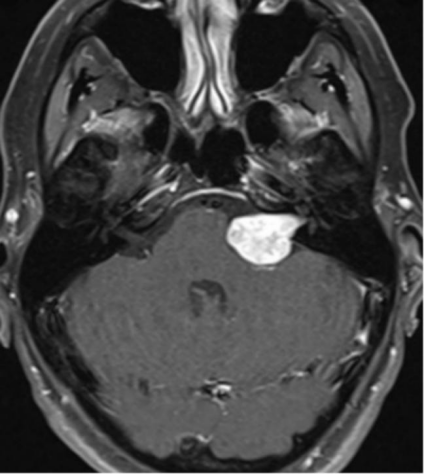

简要病史:27岁的泽洋,一名阳光帅小伙,因味觉减退,右耳听力减退(患者自觉下降50%)、耳鸣、舌头、右脸麻木2个月,头颅核磁提示右侧听神经瘤,肿...